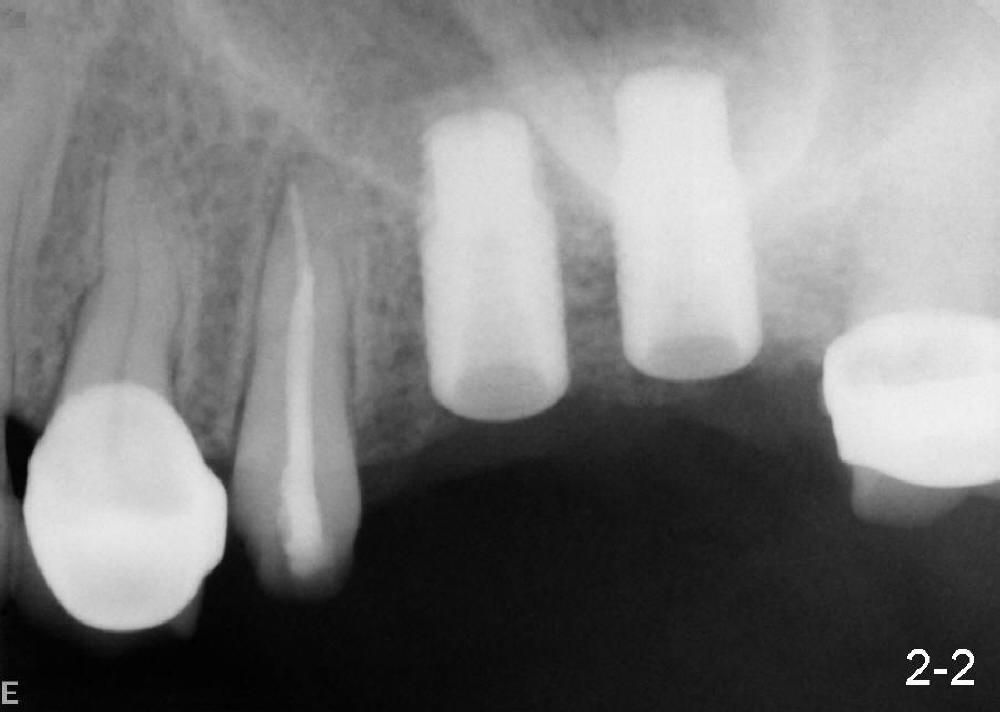

沐旭升医师送来两例植骨病例:第一例使用金属网(图一);第二例上颌骨头高度3.4 mm (CT 显示),上颌窦提高术植骨(侧面进路),同期植牙(图二)。打开每张图看评论。

Case1 is bone graft with metal mesh. Case 2 is bone graft with sinus lift through window, since the  existing bone only has 3.4 mm in the CT film (英文部分由沐医生提供).